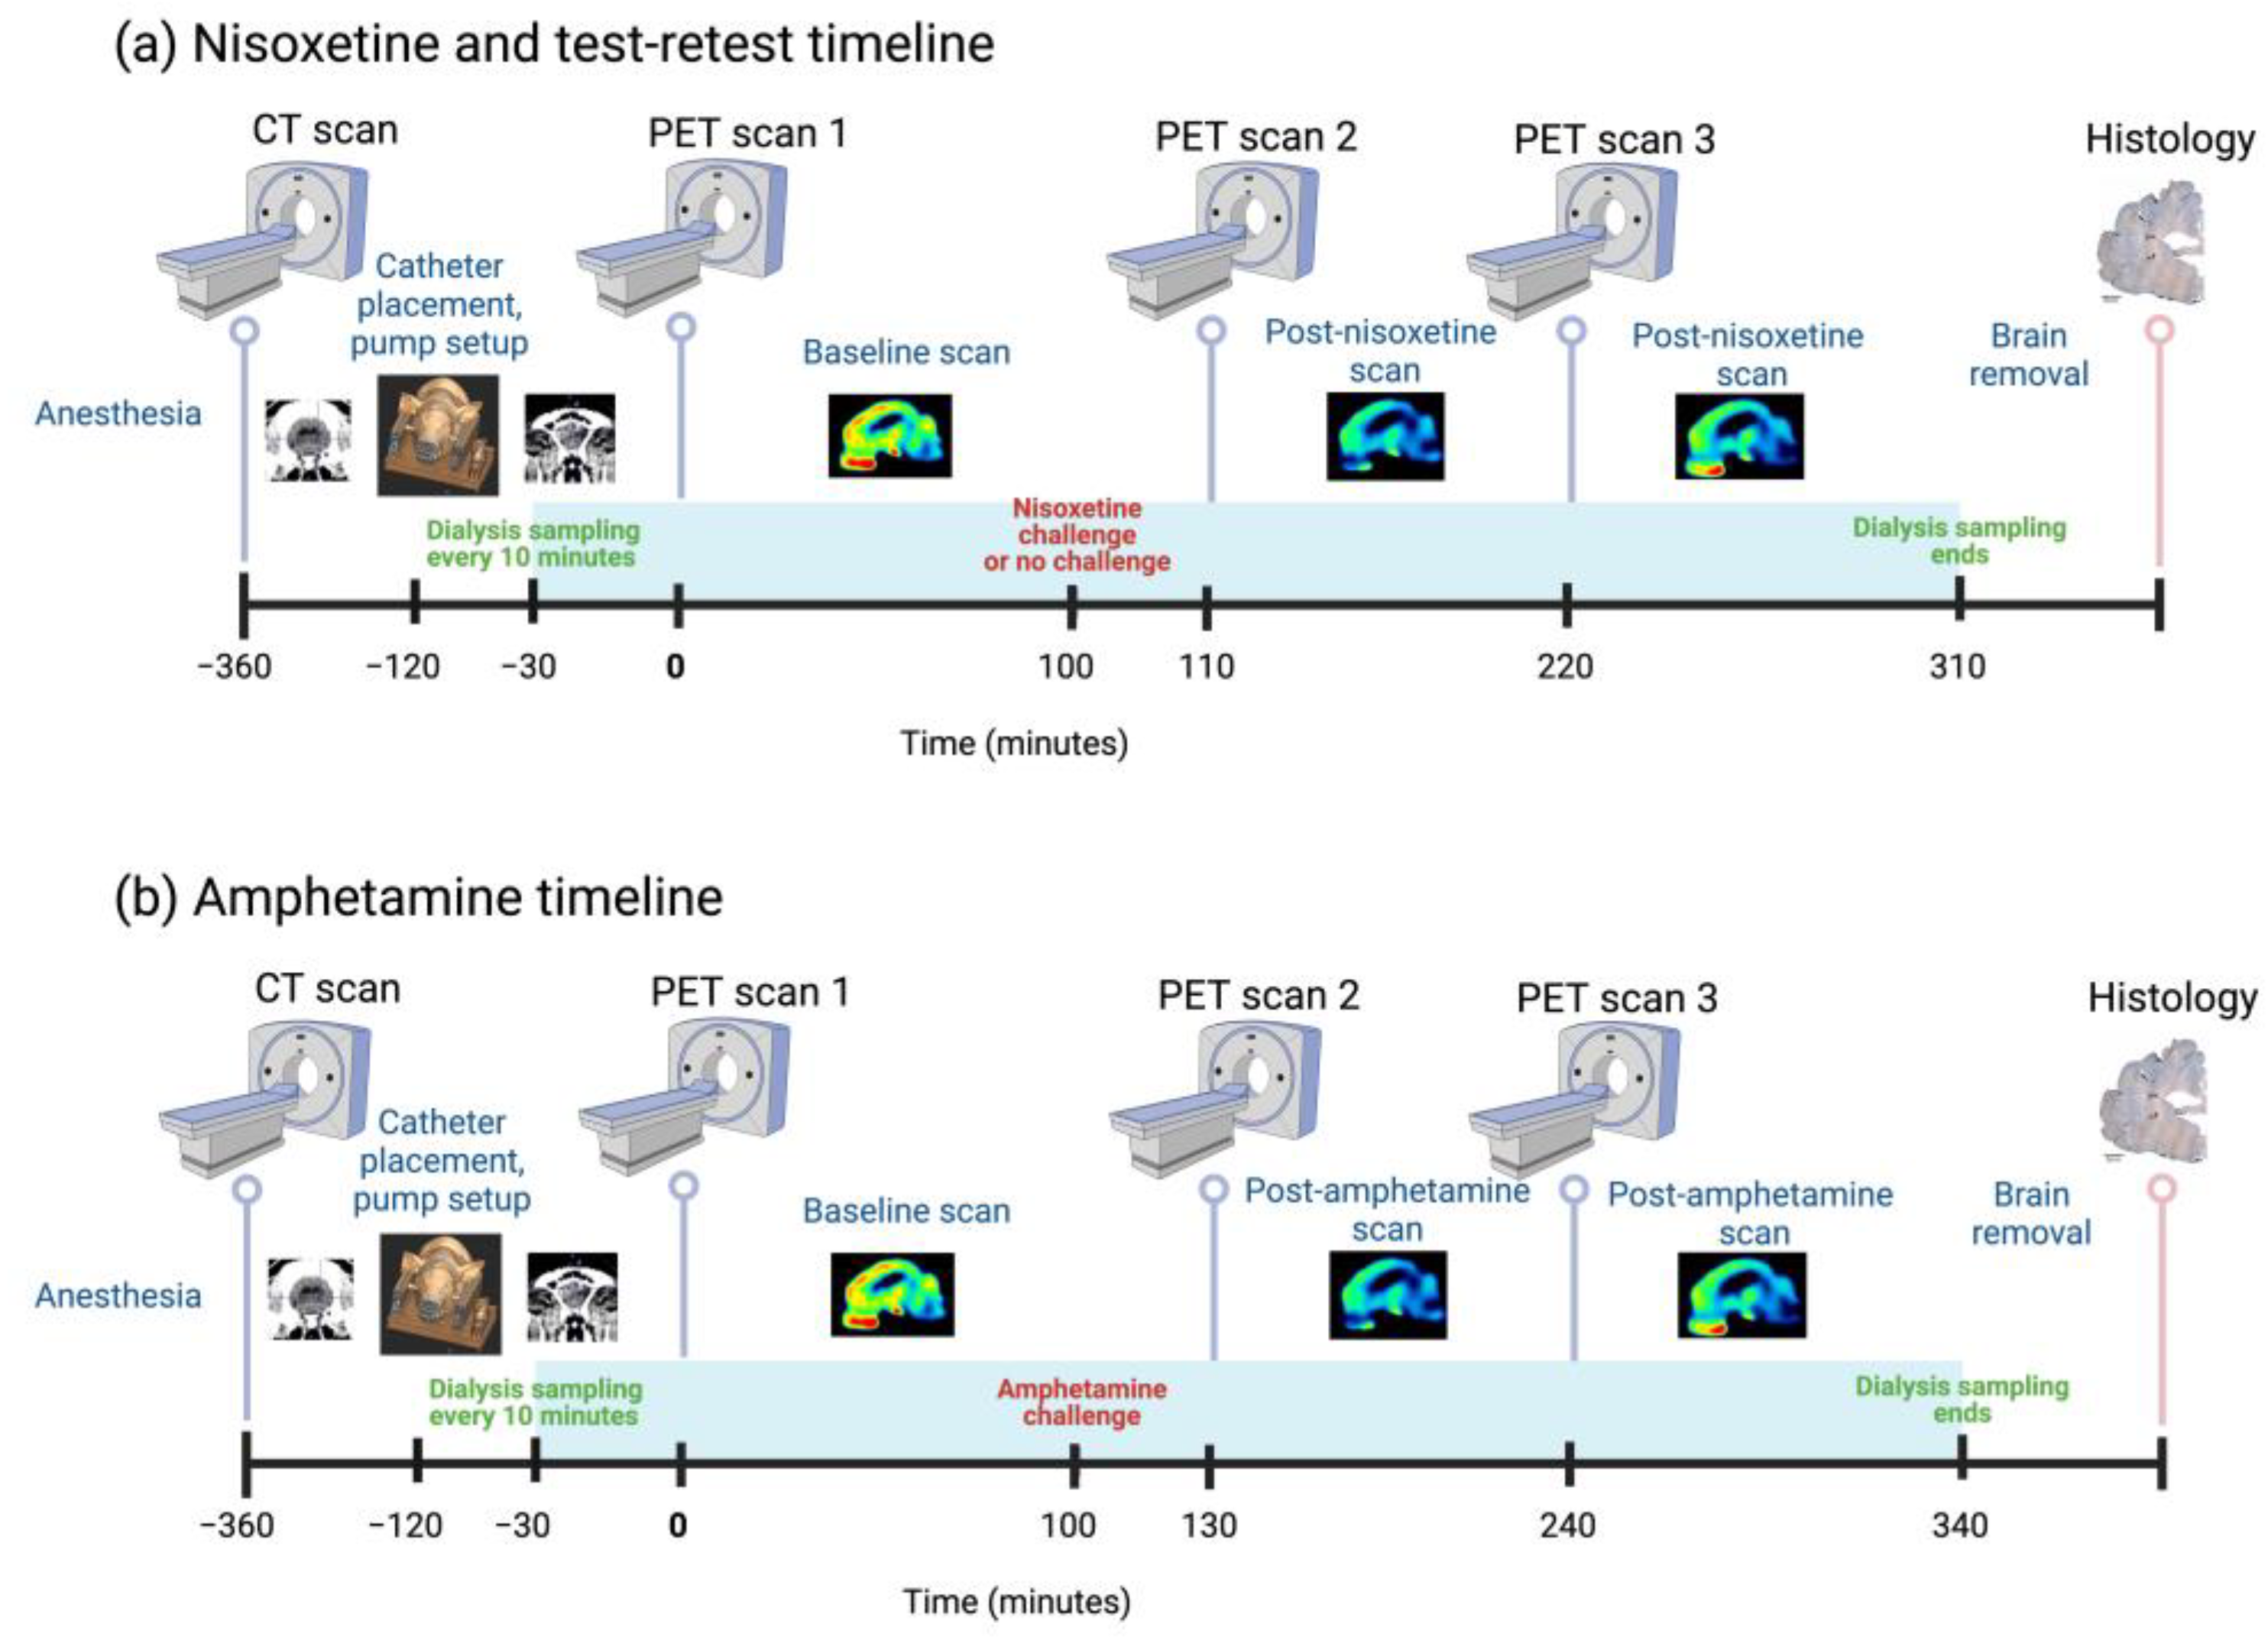

3. Results

4. Discussion